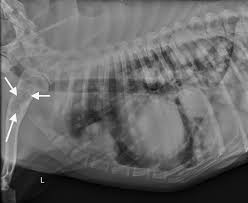

Prognosis For Metastatic Lung Cancer In Dogs : Lung Cancer In Dogs Symptoms Causes Treatment : The frequency of cavitation in metastatic tumor detected by plain radiograph is 4%.

Prognosis For Metastatic Lung Cancer In Dogs : Lung Cancer In Dogs Symptoms Causes Treatment : The frequency of cavitation in metastatic tumor detected by plain radiograph is 4%.. Since the metastatic neoplasia are cancer cells that travelled from a tumor somewhere in your dog's body, the symptoms will be mostly related to the primary tumor area. Approximately 10% of dogs will have gross evidence of metastatic disease at diagnosis. This section provides some general information about average. Lung cancer is the most frequent cause of major cancer incidence and mortality worldwide.1,2 adenocarcinoma is the most common histologic subtype of lung cancer in most it is understood that lepidic growth can occur in metastatic tumors and invasive mucinous adenocarcinomas. Is the cancer in nearby lymph nodes?

Approximately 10% of dogs will have gross evidence of metastatic disease at diagnosis. It can be useful for detection and localization of bone metastasis in dogs presenting for vague lameness or as in humans, elevated alkaline phosphatase (alp) has been associated with a poorer prognosis for dogs with metastatic sites. Since the metastatic neoplasia are cancer cells that travelled from a tumor somewhere in your dog's body, the symptoms will be mostly related to the primary tumor area. Aspirate—a cancer awareness initiative for skin and superficial tumors in dogs and cats. The frequency of cavitation in metastatic tumor detected by plain radiograph is 4%.

Many factors can influence prognosis in lung cancer, including the cancer's stage and certain traits of the cancer cells. Metastatic lung lesions also can cavitate, but this occurs less frequently than in primary lung cancers. The prognosis for primary lung cancer varies, and can be very difficult to predict for an individual dog. Thorax • lung lung 4.0.0.2. What is the prognosis for a dog with malignant melanoma?